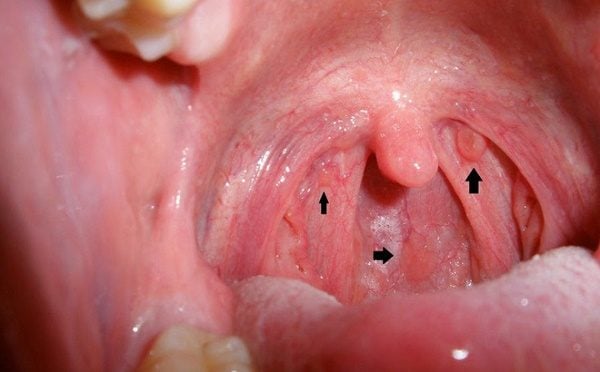

Ung thư miệng

Ung thư miệng là do sự tăng trưởng và sinh sản không kiểm soát của các tế bào ở một số vùng của miệng. Tế bào ung thư có thể xuất hiện ở má, dưới hoặc trước lưỡi, trên lớp mô của miệng hoặc nướu răng.

Nam giới hút thuốc hoặc nhai thuốc lá có nguy cơ phát triển ung thư miệng cao. Các triệu chứng ung thư miệng thường gặp là:

- Vết loét lâu lành trong miệng

- Khó nhai hoặc nuốt

- Xuất hiện khối u hoặc vùng đau nhức ở miệng, họng, trên môi

- Khó cử động lưỡi hoặc hàm

- Đau hoặc loét không liền, chảy máu

- Sưng nề, đau trong miệng

Những triệu chứng nêu trên cũng có thể là dấu hiệu của nhiều bệnh lý lành tính ở vùng miệng họng khác nên nhiều nam giới chủ quan. Việc không đi khám ngay khi có dấu hiệu bất thường khiến bệnh tiến triển nặng hơn.

Ung thư miệng nếu được phát hiện và điều trị kịp thời, tỷ lệ chữa khỏi cao hơn việc phát hiện và chữa trị ở giai đoạn muộn.